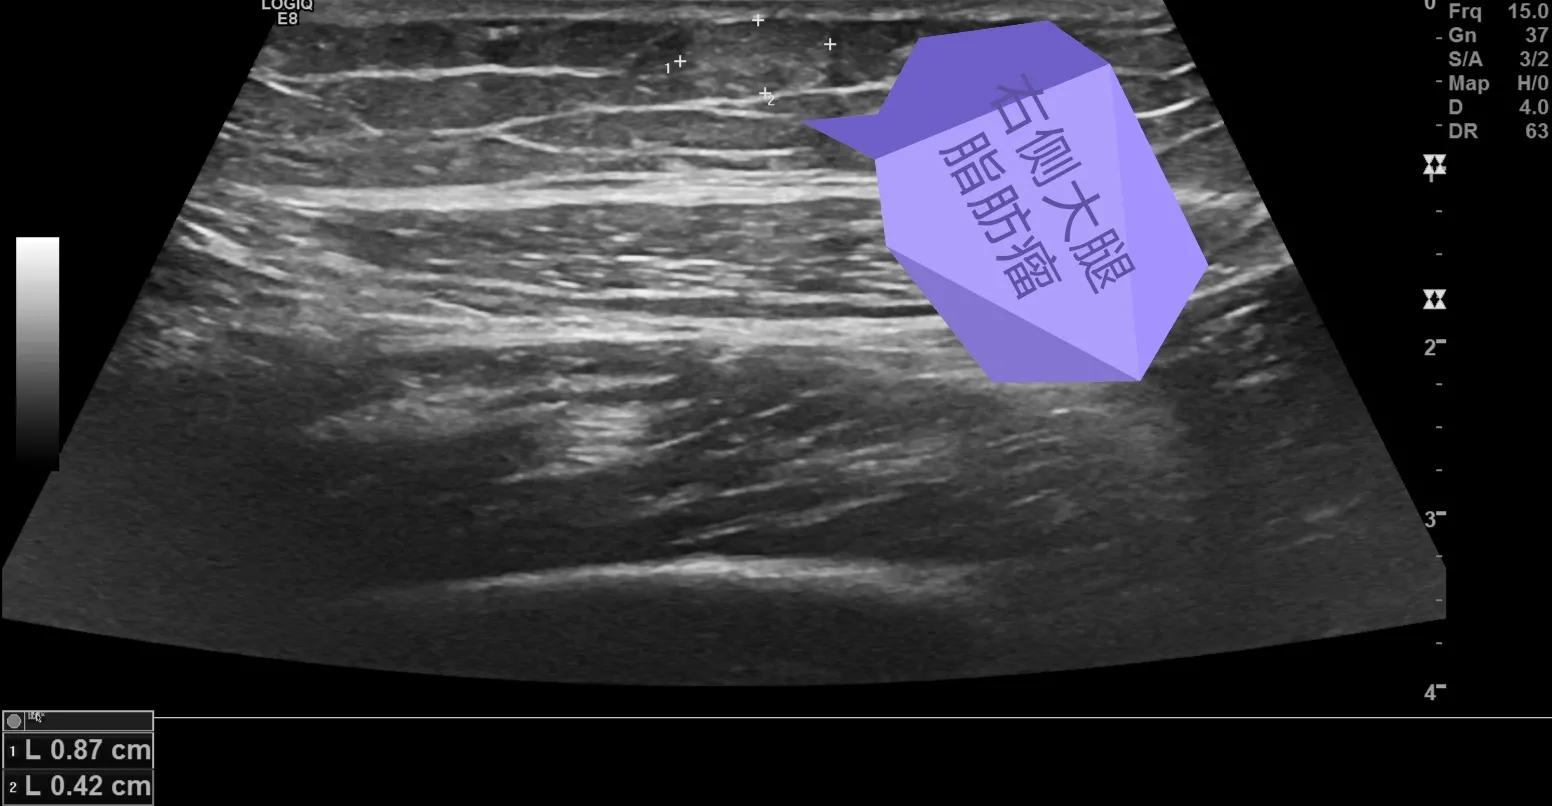

下面给大家分享几个我平时做的病例,发生在各个部位的脂肪瘤。

低回声的脂肪瘤,无血流信号